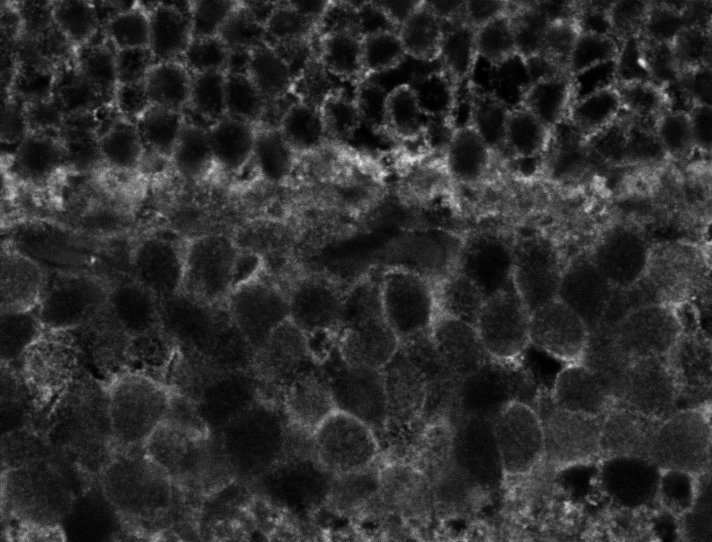

Unhealthy Retina

Unhealthy Choroid